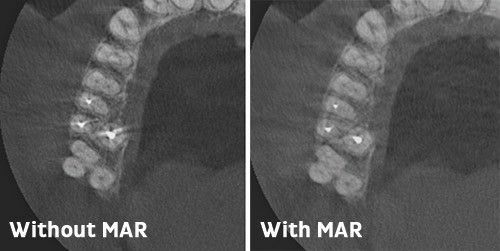

Более четкие изображения с технологией MAR

Выбираемый пользователем алгоритм уменьшения влияния артефактов, возникающих от металлов в челюсти (MAR), снижает воздействие отраженного излучения, появляющегося в облучаемых областях от объектов с высокой плотностью. Таким образом, оптимизируется визуализация зубов с запломбированными корневыми каналами.